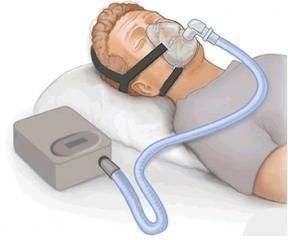

持續氣道(dào)正壓(CPAP)治療是(shì)阻塞性睡(shuì)眠呼吸暫停的(de)一(yī)線治療。CPAP呼吸機(jī¥)通(tōng)過在您睡(shuì)覺時(shí)戴的(de)口罩輕輕地(dì)提供恒定的(de)氣流,從(cóng)而在夜間(jiān)保持呼吸道(dào)通(tōng)暢。造成這(zhè<)消除了(le)呼吸暫停睡(shuì)眠呼吸暫停,

因此你(nǐ)将不(bù)再打鼾或不(bù)再有(yǒu)睡(shuì)眠窒息的(de)聲音(yīn)。您将可(kě)以整夜睡(shuì)±眠,而無需因缺氧而醒來(lái)。

每天晚上(shàng)使用(yòng)CPAP呼吸機(jī)時(shí),白(bái)天會(huì)更加精神,您的σ(de)心情會(huì)有(yǒu)所改善,并且您的(de)記憶會(huì)更好(hǎo)。

CPAP呼吸機(jī)可(kě)以預防甚至治療與睡(shuì)眠呼吸暫停有(yǒu)關的(de)嚴重健康≈問(wèn)題,例如(rú)心髒病和(hé)中風(fēng)。

CPAP呼吸機(jī)配有(yǒu)機(jī)器(qì),軟管和(hé)面罩。大(dà)多(duō)數(shù)機(jī)器(qì)很(hěn)小(xiǎ✘o)-大(dà)約隻有(yǒu)紙(zhǐ)巾盒的(de)大(dà)小(xiǎo)-重量輕且相(xiàng)對(duì)安靜(jìng)。您可(kě)以'将CPAP機(jī)器(qì)放(fàng)在床頭櫃上(shàng)或床邊。

管道(dào)将CPAP機(jī)器(qì)連接到(dào)您的(de)面罩。管道(dào)足夠長(cháng)可(kě)以讓您ε在床上(shàng)移動或翻身(shēn)。

CPAP呼吸機(jī)面罩可(kě)能(néng)隻覆蓋您的(de)鼻子(zǐ)或鼻子(zǐ)和(hé)嘴巴。另一(yī)種選擇是(shì)使用(yòng)适合您鼻孔的(≠de)“鼻枕”。無論您使用(yòng)哪種類型的(de)口罩,重要(yào)的(de)是(shì)要(yào)貼合好(hǎo)用(yòng)且舒适。面罩必須密封,以保持通(tōn₽g)氣通(tōng)宵通(tōng)宵。良好(hǎo)的(de)面罩密封将防止空(kōng)氣洩漏并保持适當的(de)氣壓水(sh→uǐ)平。

您的(de)睡(shuì)眠醫(yī)生(shēng)将确定CPAP呼吸機(jī)治療您的(de)睡(shuì)眠呼吸暫停所需的(de)氣壓量。醫(yī)生(shēng)可(kě)能(néng≈)會(huì)建議(yì)進行(xíng)CPAP呼吸機(jī)滴定研究以校(xiào)準您的(de)氣壓設置。大(dà)多(duō)數(shù)CPAP裝置還(hái)帶有♥(yǒu)延時(shí)升壓設置。這(zhè)會(huì)以非常低(dī)的(de)水(shuǐ)平啓動氣流,因此您可(k•ě)以舒适地(dì)入睡(shuì)。然後該設置會(huì)在您睡(shuì)覺時(shí)緩慢(màn)增加壓力,直到(dào)達到(dào)治療睡(shuì)眠呼×吸暫停的(de)正确水(shuǐ)平。